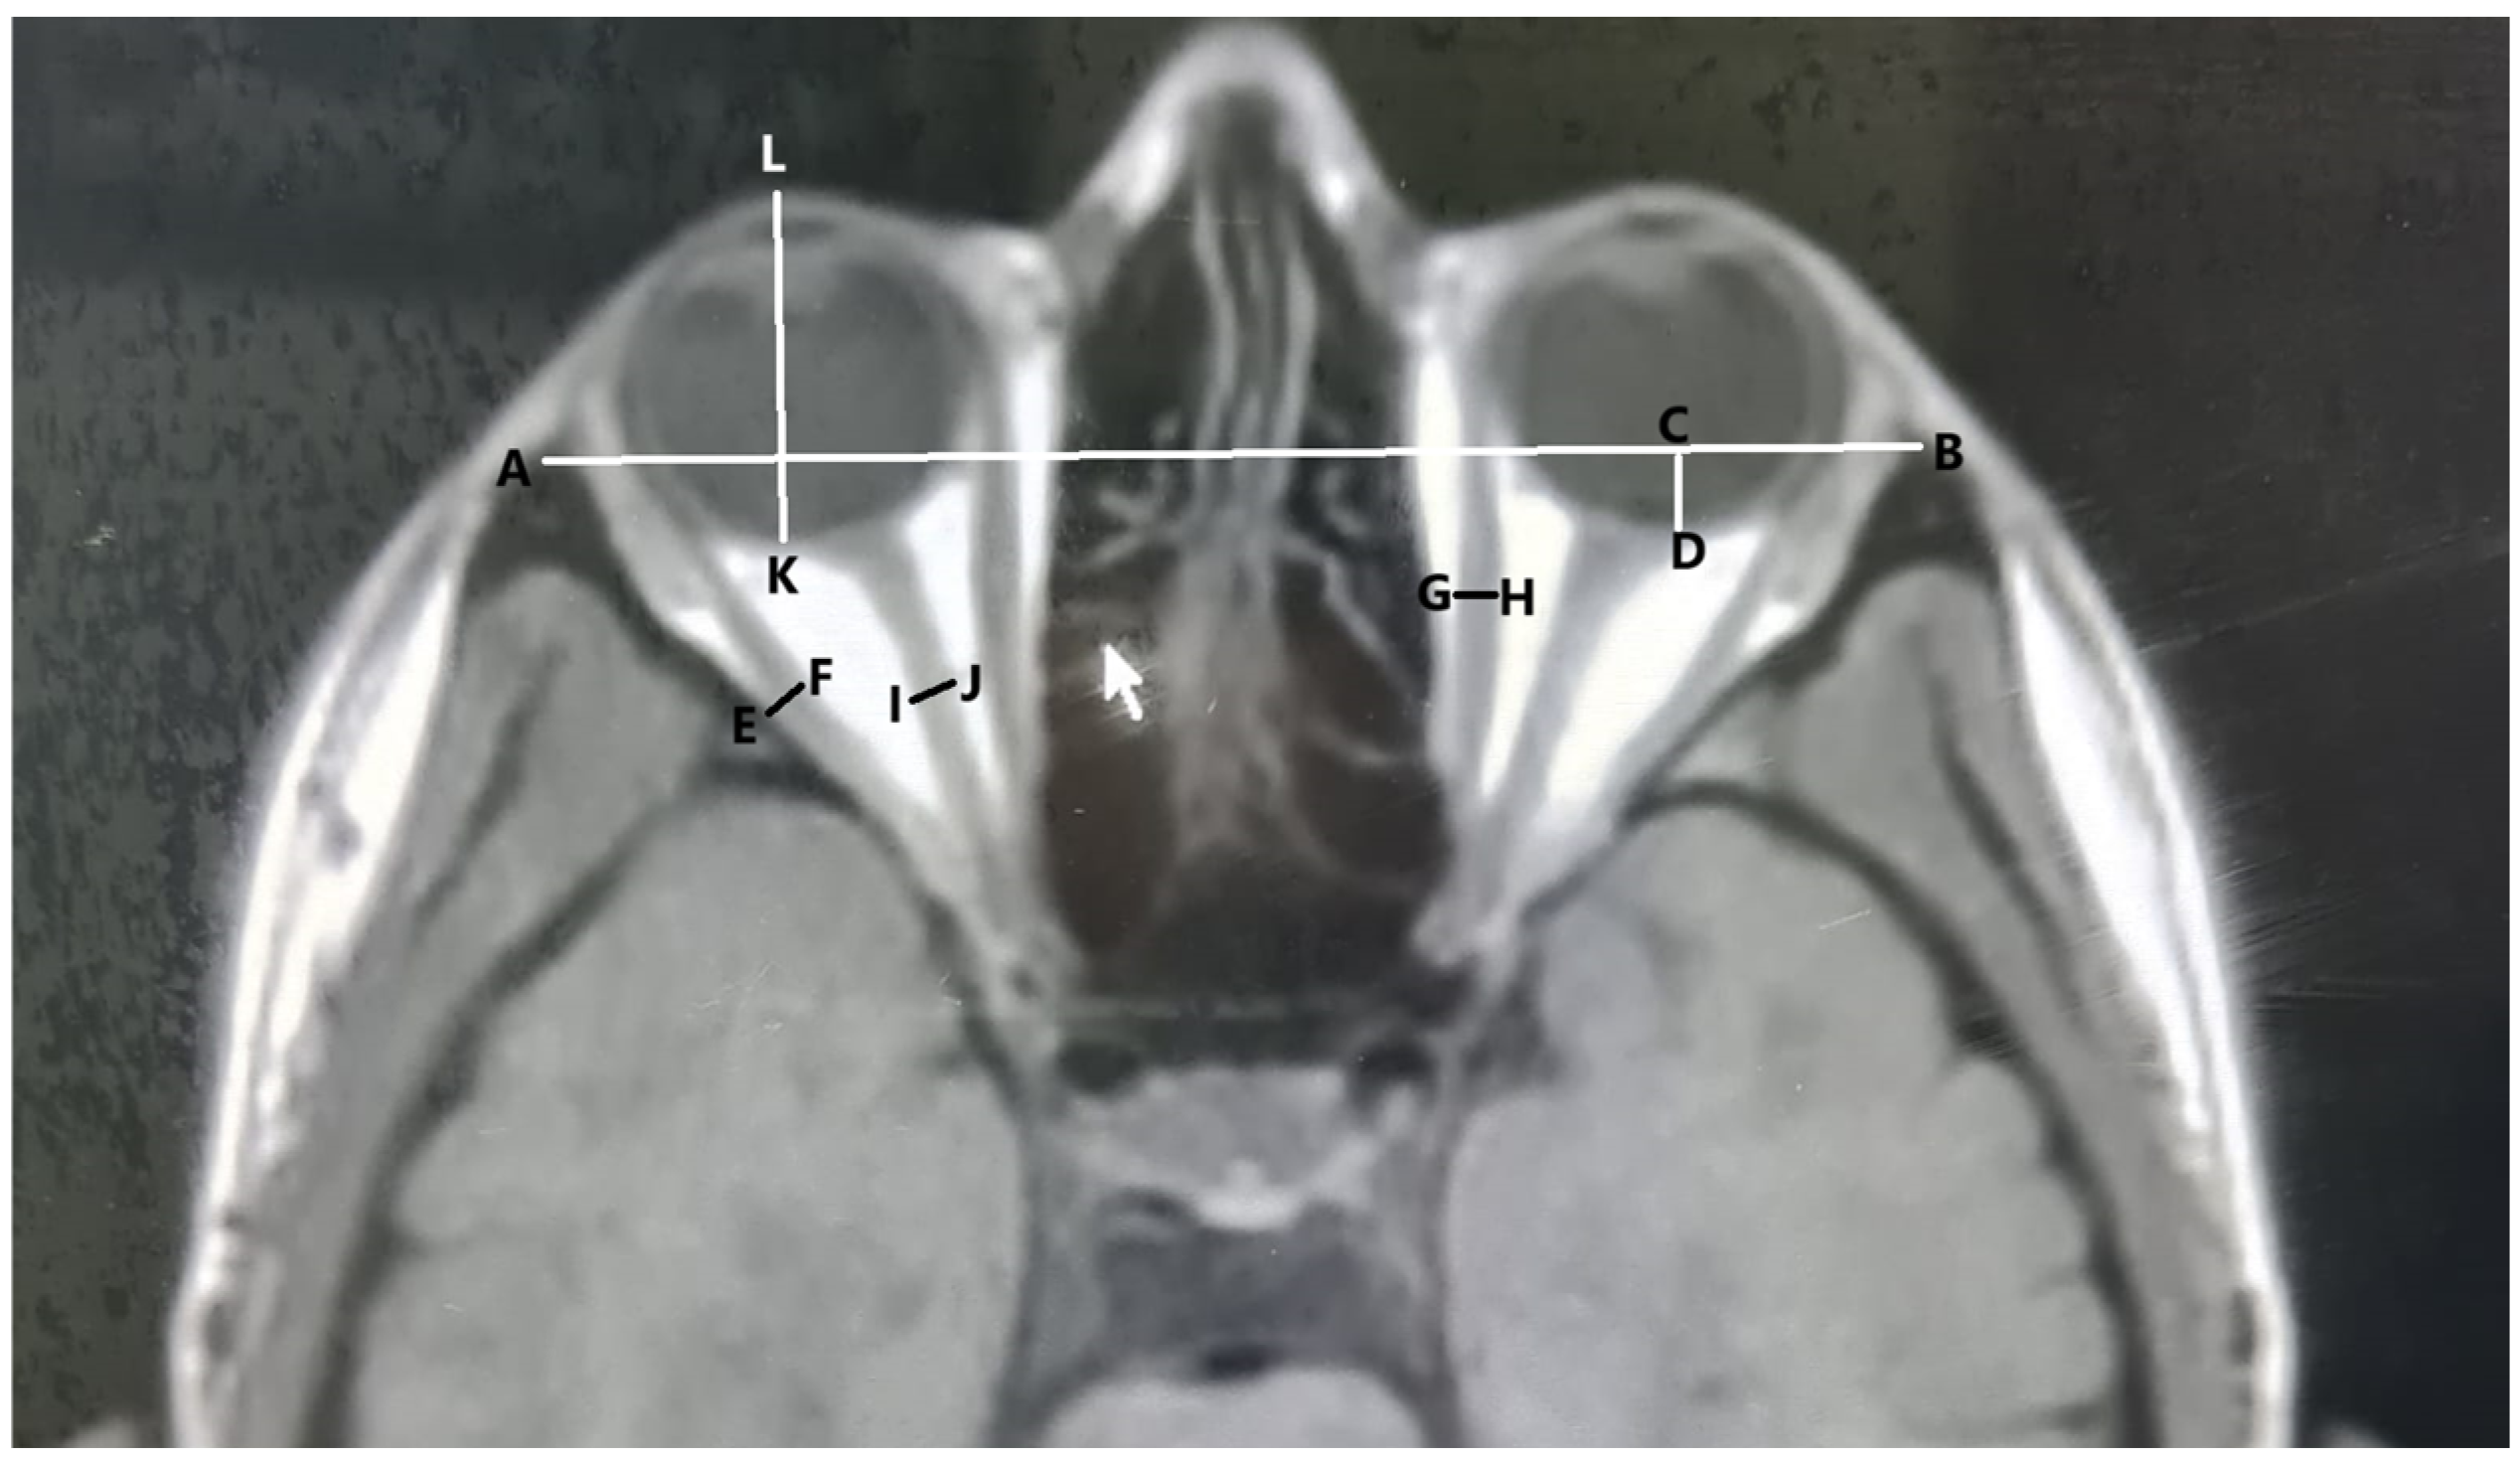

- The length of the interzygomatic line: This line was measured on axial images at the mid-globe position (Figure 1).

- Globe position: The distance between the interzygomatic line and posterior margin of the globe. It was measured perpendicular to the interzygomatic line on axial images in the mid-globe position (Figure 1).

- Ocular bulb length: The distance between the posterior surface of the cornea and posterior pole of the ocular bulb was measured in the mid-globe position on axial images (Figure 1).

- Optic nerve sheath diameter: Optic nerve sheath diameter was measured in axial sections from the area where the middle part of the nerve was visible, cutting the nerve course perpendicularly (Figure 1).

- The diameters of the lateral and medial rectus muscles: The horizontal diameter was measured from the widest area in the axial scans (Figure 1).